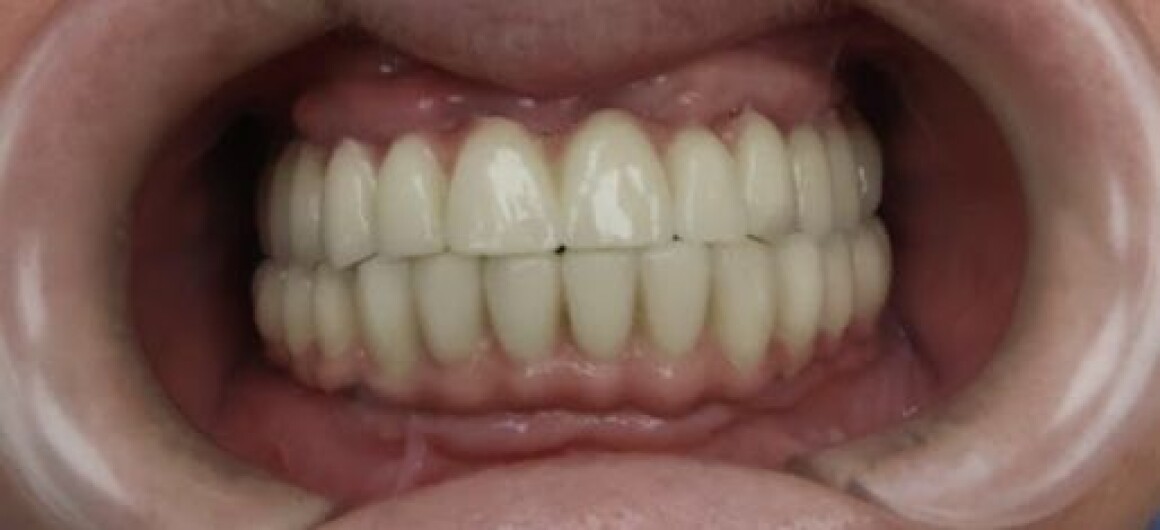

Тотальная реабилитация

Проблема : Полное отсутствие зубов, не держаться протезы

• Установка постоянной конструкции из металлокерамики верх и низ

720 900 Р

5 месяцев

12 месяцев